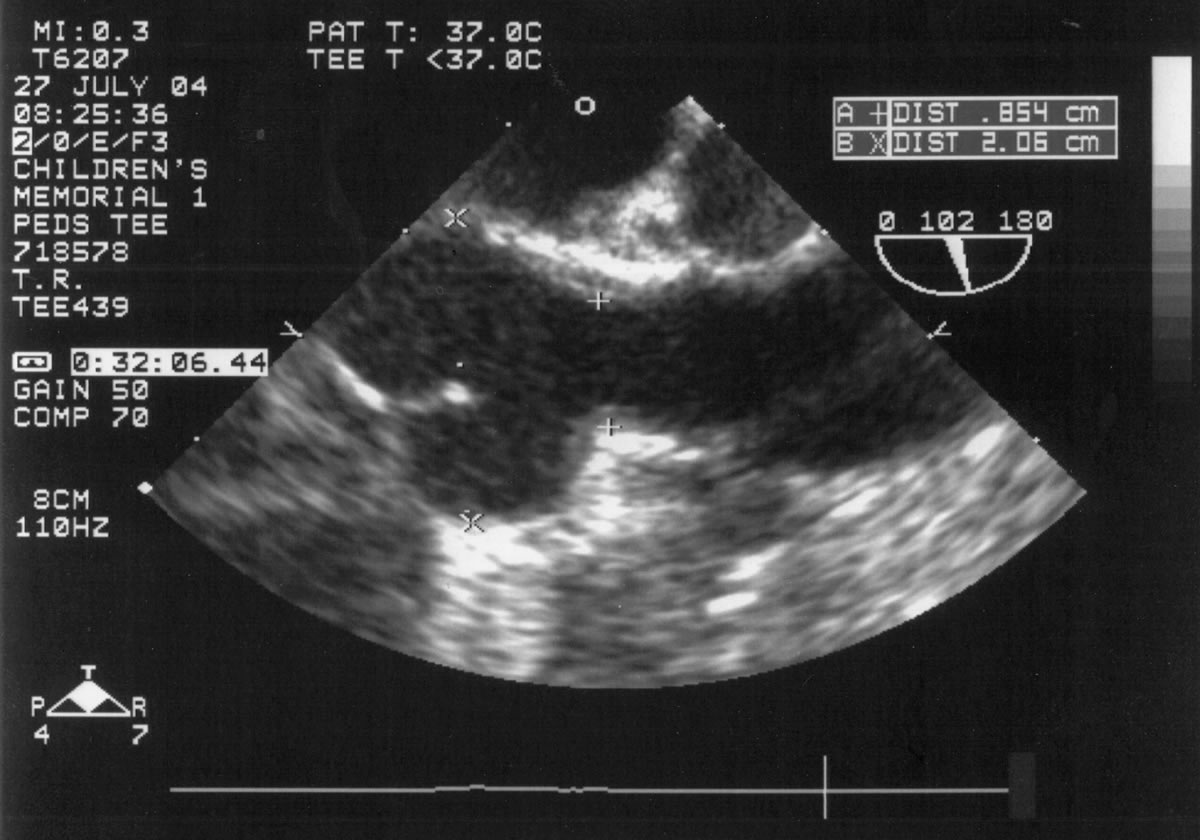

An asymptomatic, 5-year-old, 18-kg boy known by genetic testing to have Williams syndrome on physical examination had a IV/VI harsh systolic ejection murmur and no diastolic murmur. Preoperative echocardiogram showed an aortic root dimension of 2 cm and the dimension at the level of stenosis in the ascending aorta was 8 mm. Peak echocardiogram gradient was 70 mm Hg with a cardiac catheterization gradient of 50 mm Hg. The child had no peripheral pulmonary artery stenosis.

Preoperative transesophageal echocardiogram in long-axis view shows ascending aorta with aortic valve to the left. The markers indicate the aoritc root dimension to be 2.0 cm and hte mid portion of the stenosis to be 0.8 cm.